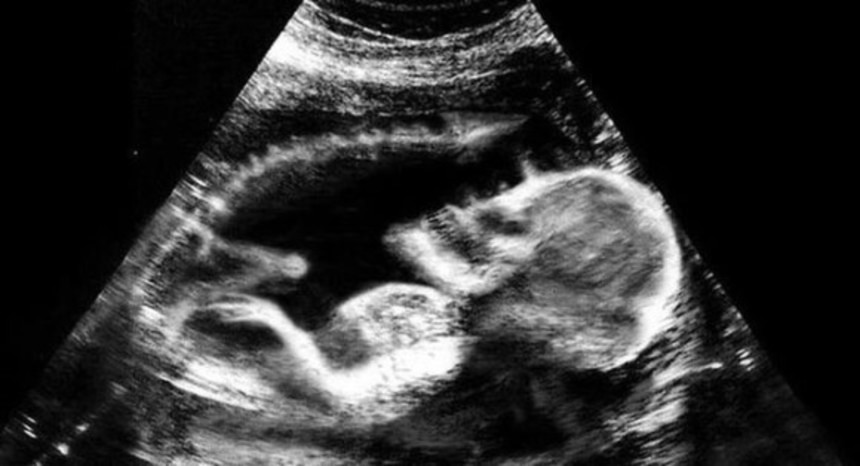

人間の脳は、3つの点が集まった図形を人の顔と見るようにプログラムされているようにできている。これはシミュラクラ現象と呼ばれるものなのだが、モノクロで撮影された胎児の超音波写真は、見方によってはホラーとしか言えない悪夢的光景が潜んでいるようなんだ。

これらの超音波写真は、親御さんがネット上で公開したもので、見方によっては腹にやばいものが宿っているように見えるものだ。

ロールシャッハ・テストじゃないけれど、人によってはまったく違ったものが見えてくるかもしれない。